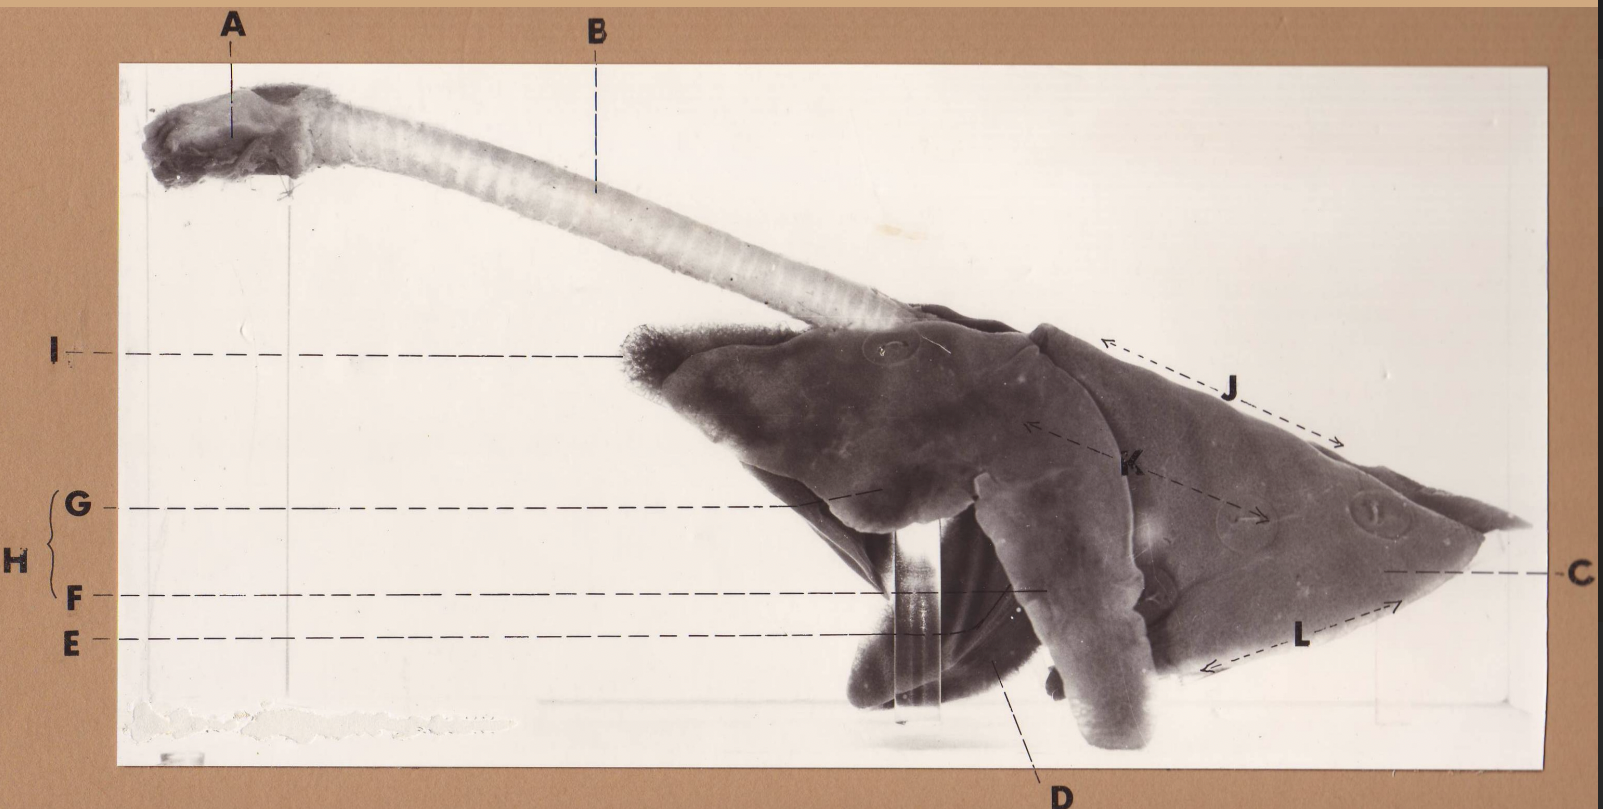

A

(cat larynx/trachea/lungs, L lateral)

larynx

B

(cat larynx/trachea/lungs, L lateral)

trachea

C

(cat larynx/trachea/lungs, L lateral)

caudal lobe

D

(cat larynx/trachea/lungs, L lateral)

middle lobe

E

(cat larynx/trachea/lungs, L lateral)

cardiac notch

F

(cat larynx/trachea/lungs, L lateral)

caudal segment, cranial lobe

G

(cat larynx/trachea/lungs, L lateral)

cranial segment, cranial lobe

H

(cat larynx/trachea/lungs, L lateral)

cranial lobe

I

(cat larynx/trachea/lungs, L lateral)

apex

J

(cat larynx/trachea/lungs, L lateral)

dorsal border

K

(cat larynx/trachea/lungs, L lateral)

costal surface

L

(cat larynx/trachea/lungs, L lateral)

basal border